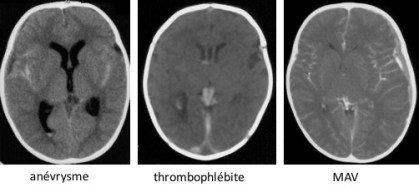

il existe d’exceptionnelles causes de saignement spontané intracrânien chez le nourrisson :

- des causes structurelles (locales)

- vasculaire(Cf.ci-dessous